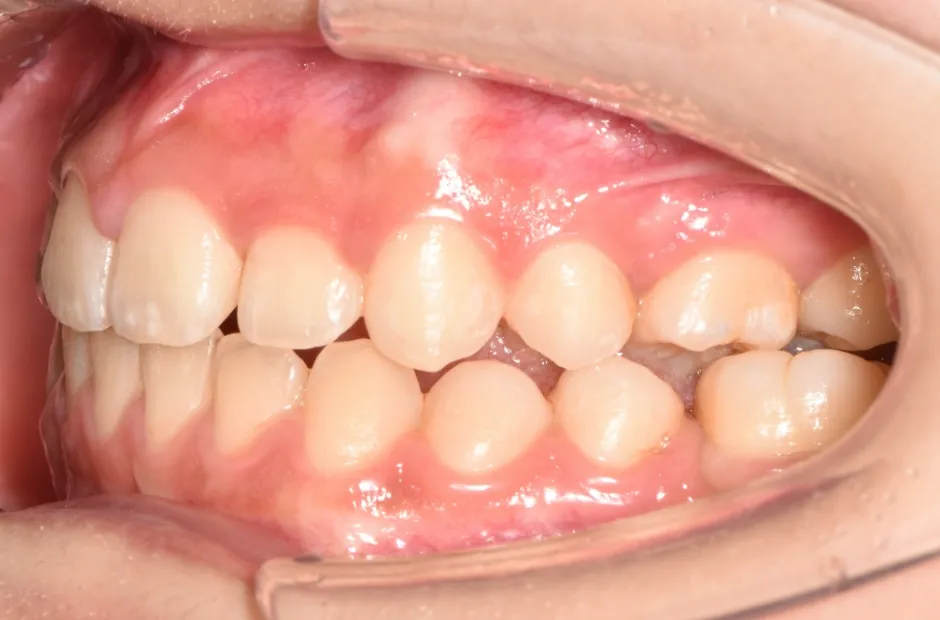

叢生

| 診断名・主訴 | 叢生 |

|---|---|

| 年齢・性別 | 43歳・女性 |

| 治療期間・回数 | 2年7か月 27回 |

| 治療に用いた主な装置 | 舌側矯正 |

| 抜歯部位 | 両顎4,4 |

| 治療費 | 100万円(税抜) |

| リスク・副作用 | 装置による違和感・疼痛・歯肉退縮・歯根吸収・虫歯のリスクなど |